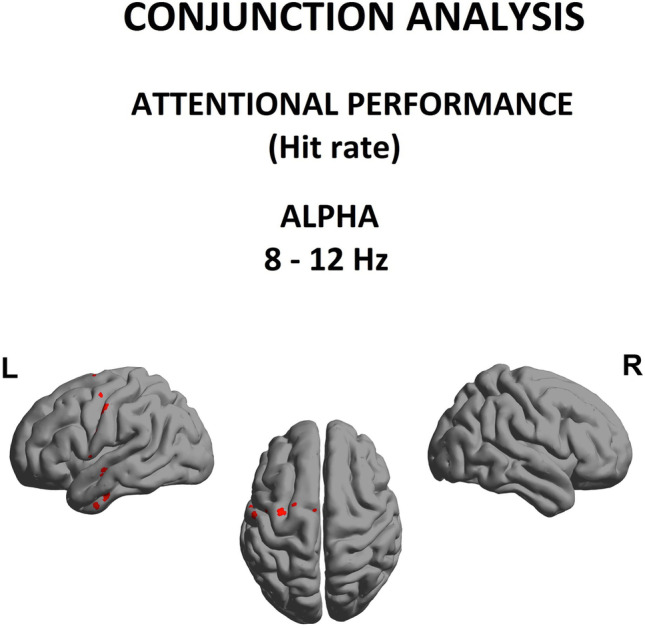

Conjunction analysis between group spectral power abnormalities and correlates of behavioral deficits

Finally, as shown in Fig. 5, we investigated whether abnormal spectral power seen at the group level was consistent with changes associated with interindividual differences in attentional performance. In other words, was there evidence for a selective disruption of alpha rhythm in cannabis addiction that impacted attentional function? Consequently, we performed a conjunction of tests (i.e., global null hypothesis) to identify the overlap, if any, between the statistically-significant (p < 0.05) group-level relative alpha power differences (Fig. 2) and the regression between relative alpha power and omission errors (Fig. 4).

Interestingly, we identified a statistically reliable overlap within alpha band and attentional performance in the left sensorimotor and temporal regions (Brodmann area 4, 6, 20 with maximum (t = 1.50, p < 0.05)).